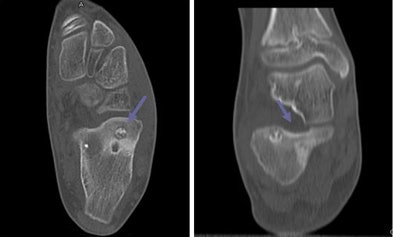

| Axial (left) and coronal (right) MDCT images of a 12-year-old with calcaneous osteoid osteoma show bone detail. |